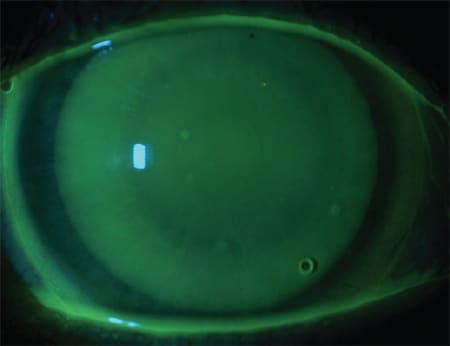

At the dispensing appointment, we applied the lenses and allowed them to settle. After settling, fluorescein was instilled into each eye and was allowed to circulate under the lenses. The fit was acceptable and the comfort was good (Figures 1 and 2). Distance vision was measured at 20/20 OD and 20/25 OS, with near vision at 20/25 OD and OS. The patient reported the comfort to be excellent with no real lens awareness. We dispensed the lenses with instruction for application, removal, care, and handling. She returned for a subsequent follow-up visit at which time she reported improved vision and no issues.

Figure 1. Case 1 So2Clear corneo-scleral lens OD.

Figure 2. Case 1 So2Clear corneo-scleral lens OS.